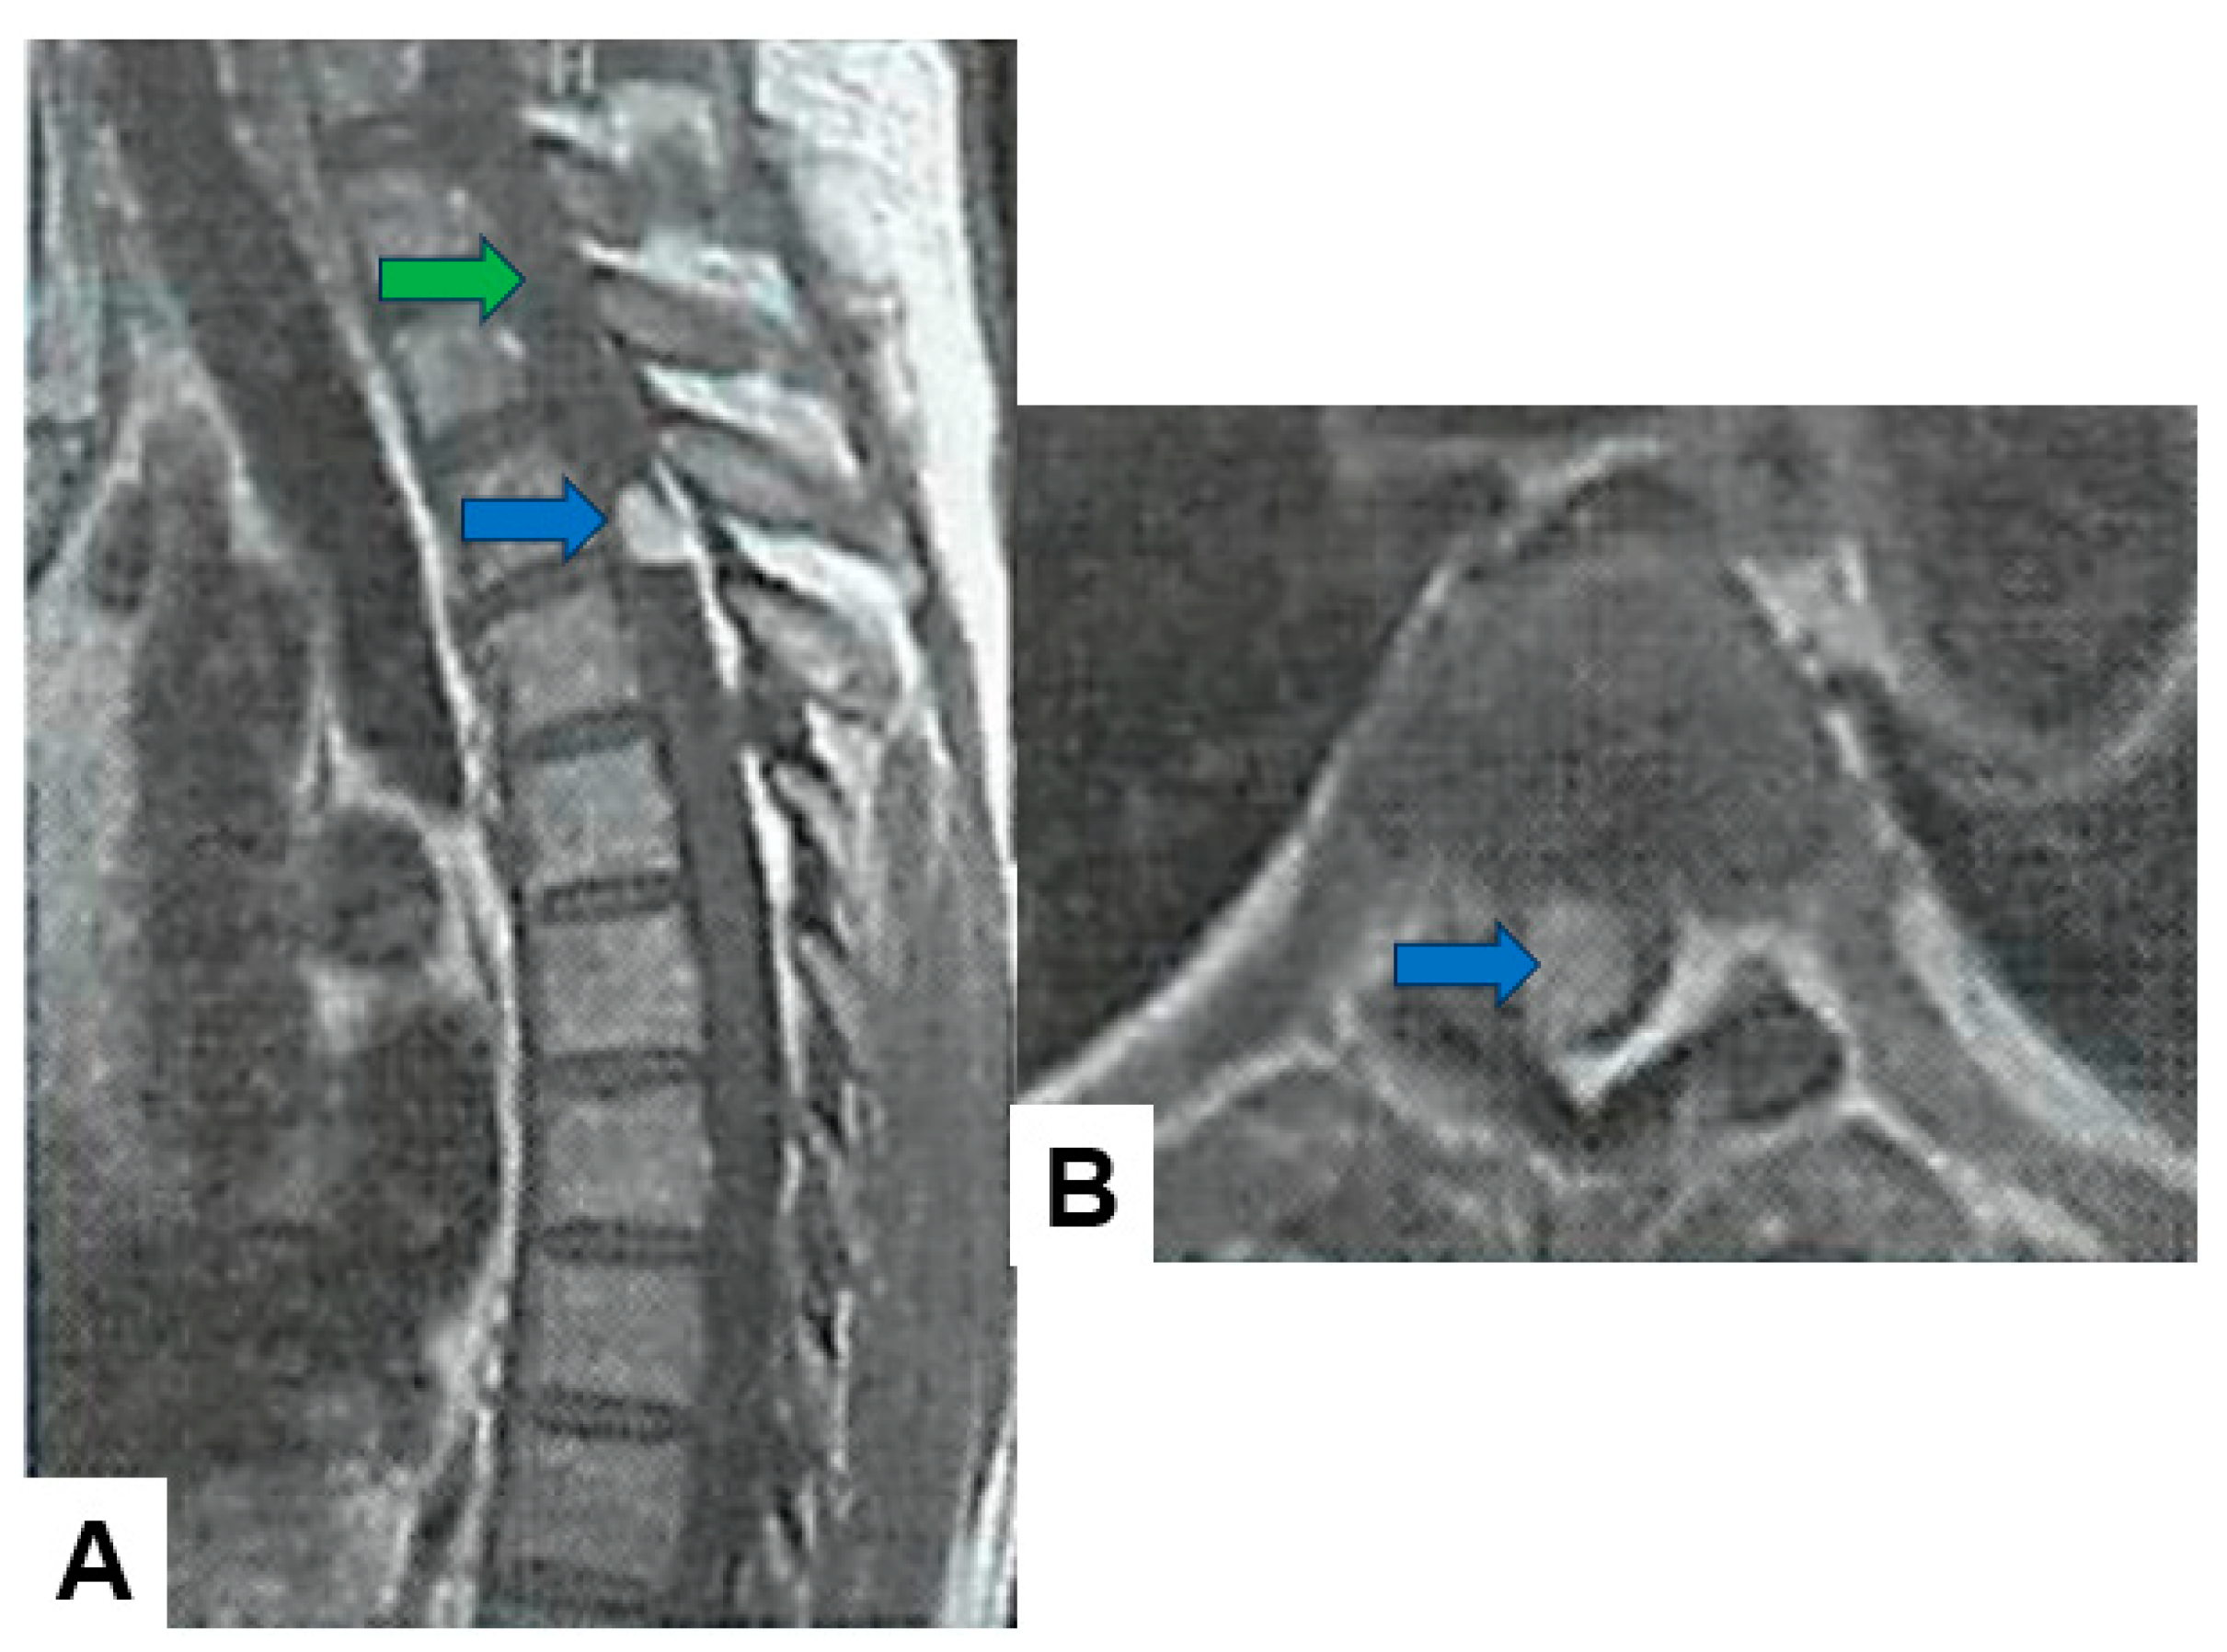

- Jung, J.S.; Choi, Y.S.; Ahn, S.S.; Yi, S.; Kim, S.H.; Lee, S.K. Differentiation between spinal cord diffuse midline glioma with histone H3 K27M mutation and wild type: Comparative magnetic resonance imaging. Neuroradiology 2019, 61, 313–322. [Google Scholar] [CrossRef] [PubMed]